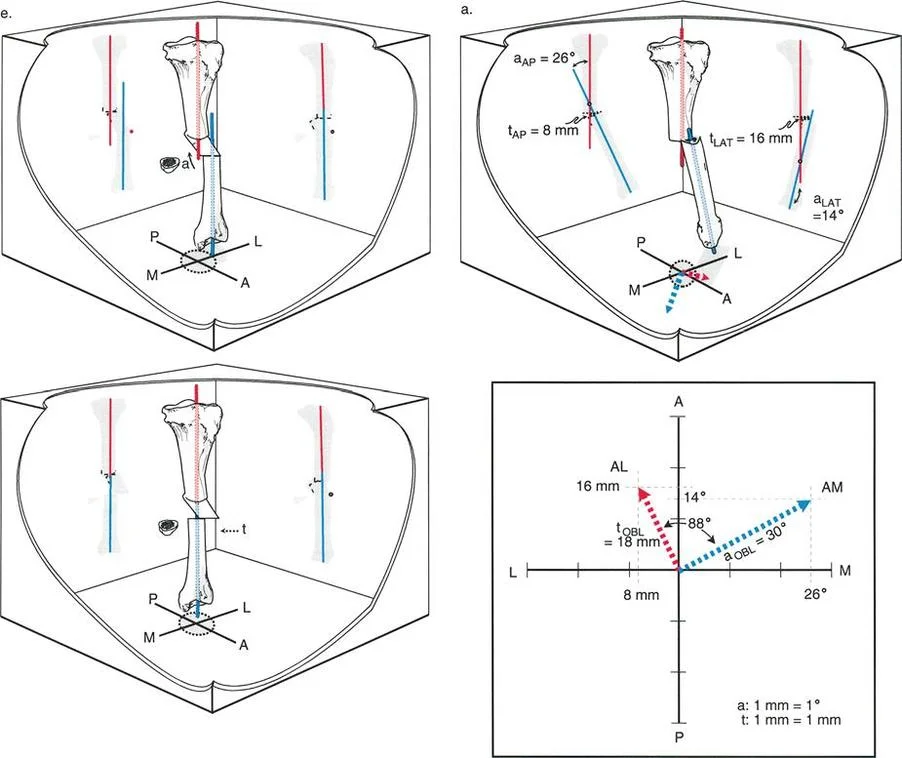

زوايا القياس الهامة:

- زاوية الانحناء البعيدة للفخذ (PDFA - Posterior Distal Femoral Angle): تقيس زاوية الجزء السفلي من عظم الفخذ. القيمة الطبيعية حوالي 84 درجة. الزيادة في هذه الزاوية (أكثر من 84 درجة) تشير إلى ارتداد فخذي.

- زاوية الانحناء القريبة للظنبوب (PPTA - Proximal Posterior Tibial Angle): تقيس زاوية الجزء العلوي من عظم الساق. القيمة الطبيعية حوالي 80 درجة. الزيادة في هذه الزاوية (أكثر من 80 درجة) تشير إلى ارتداد ظنبوبي.

- مركز دوران الزاوية (CORA - Center of Rotation of Angulation): يتم تحديد هذا النقطة على الأشعة السينية لتحديد مكان التشوه العظمي بدقة، وهو أمر بالغ الأهمية لتخطيط عملية قطع العظم.